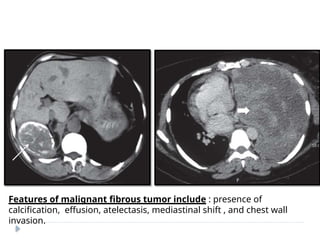

Benign pleural fibroma.

Enhanced CT reveals a soft tissue

intrafissural mass with coarse

calcifications, pathologically consistent

with a benign pleural fibroma.

Features of malignant fibrous tumor include : presence of

calcification, effusion, atelectasis, mediastinal shift , and chest wall

invasion.